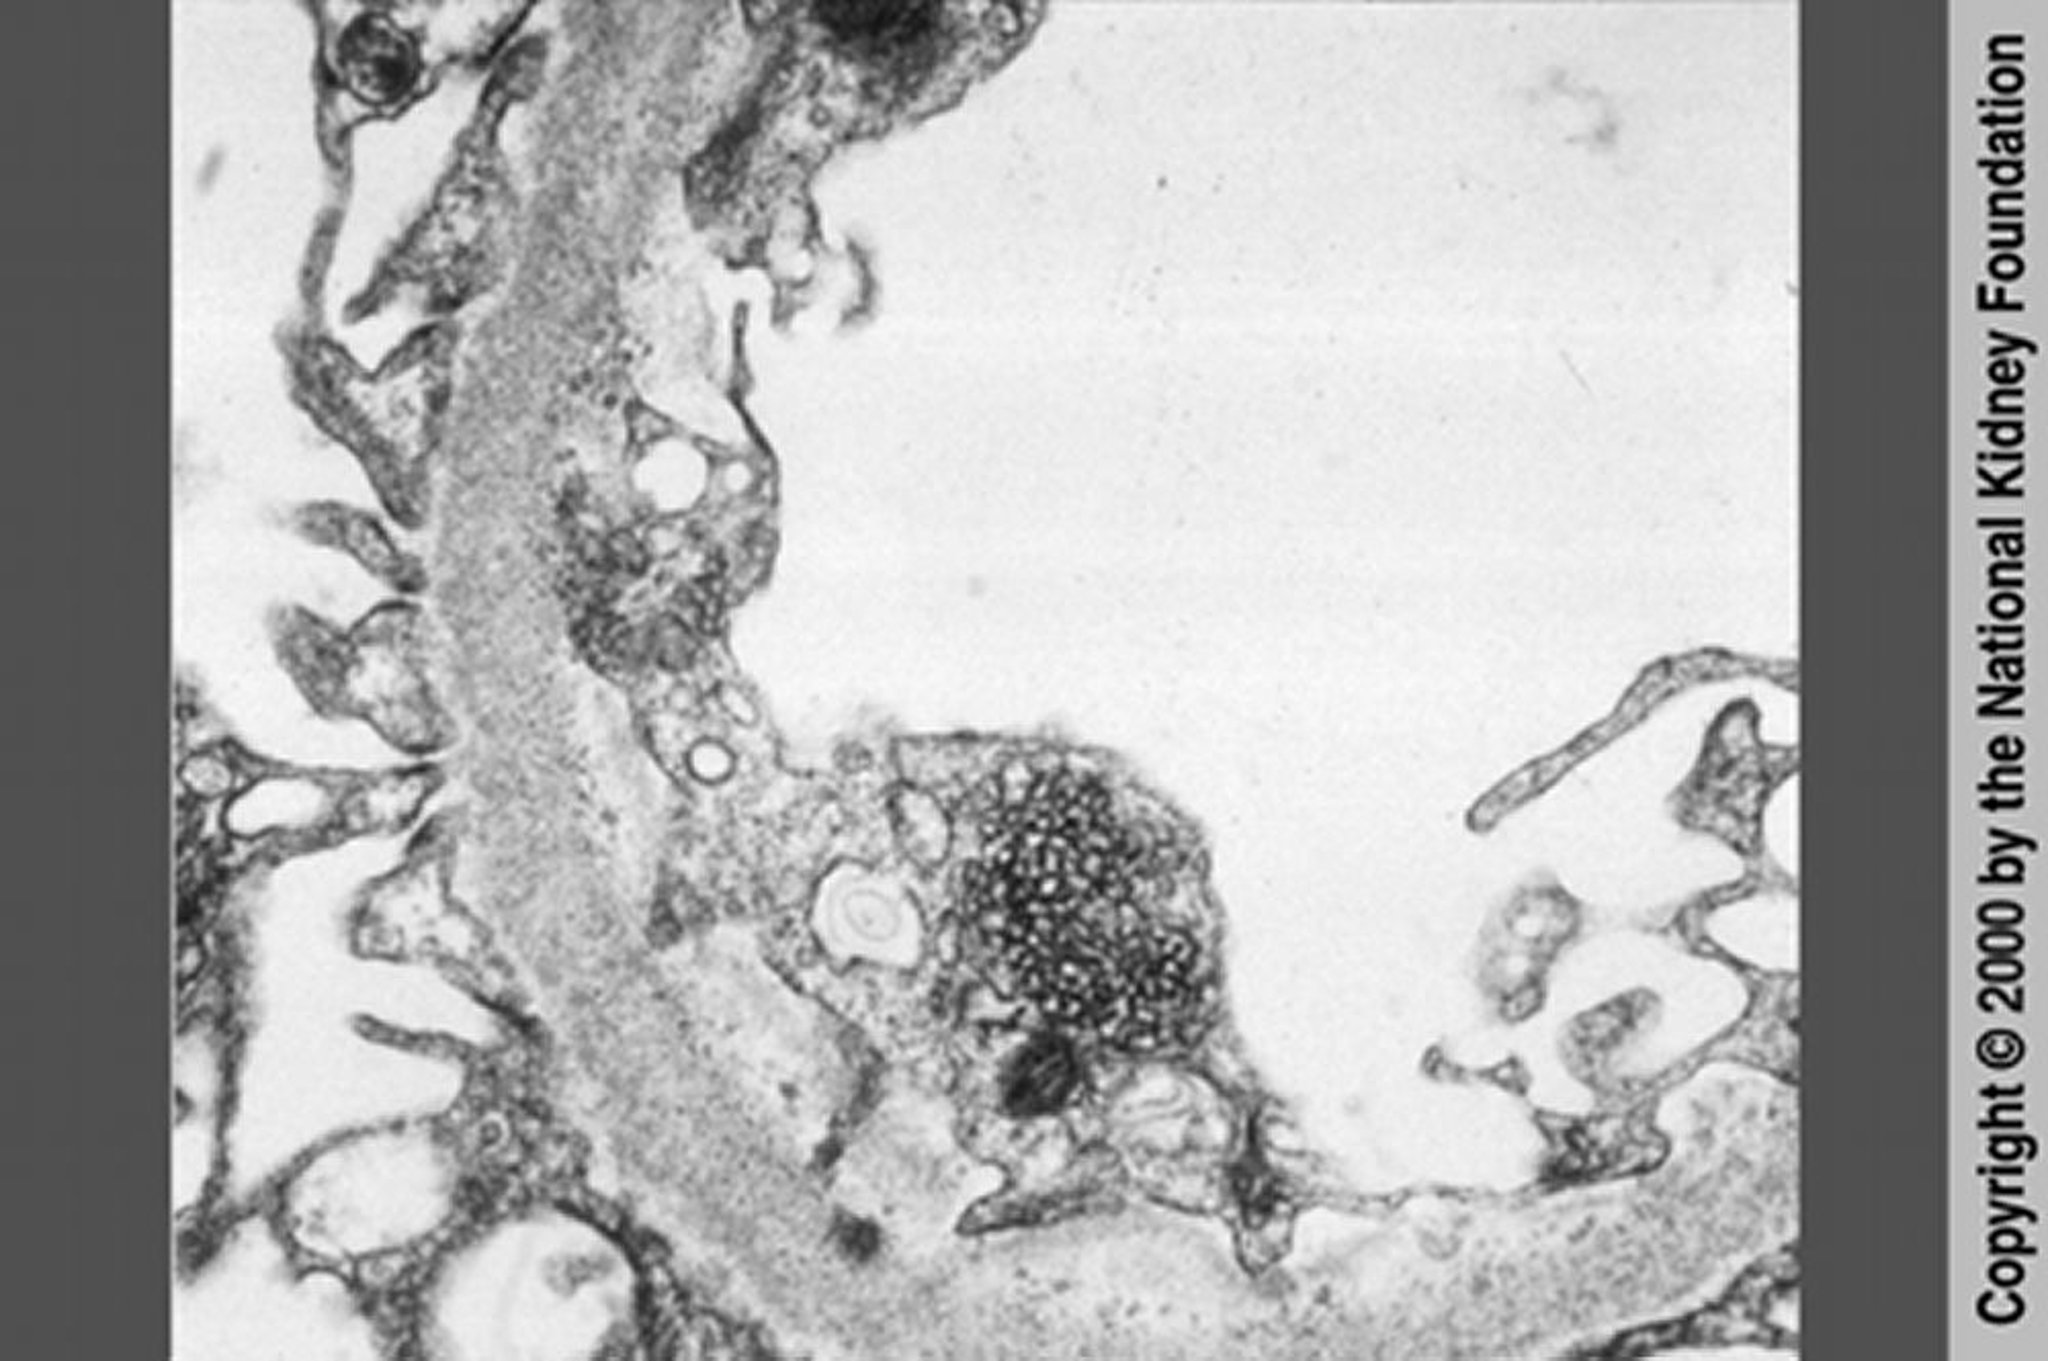

Néphropathie associée au VIH (inclusions réticulaires)

La néphropathie associée au VIH peut être distinguée de la glomérulosclérose segmentaire et focale par des inclusions réticulaires présentes dans le cytoplasme des cellules endothéliales en microscopie électronique à transmission (×20 000). Cependant, ces inclusions réticulaires sont à présent rares avec l'utilisation d'un traitement antirétroviral hautement actif.

Image fournie par Agnes Fogo, MD, and the American Journal of Kidney Diseases' Atlas of Renal Pathology (voir www.ajkd.org).